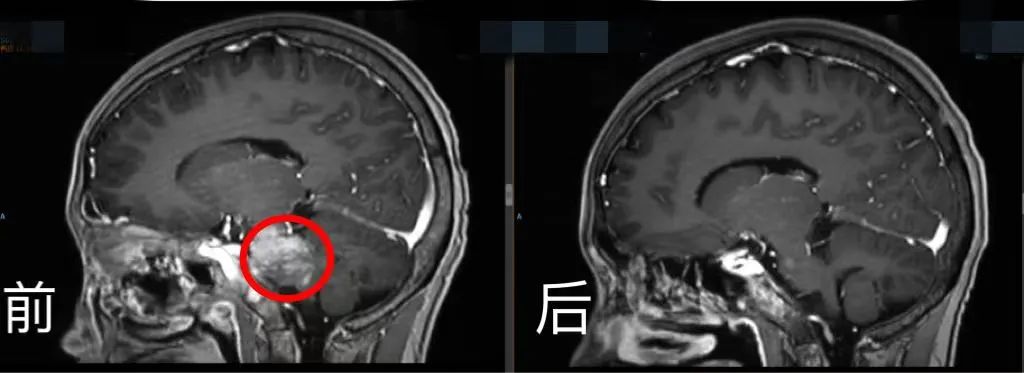

今年春節前,身體情況良好的小玉可以走著出院了。但是,半個月后,她又坐著輪椅回來了。

此時,小玉身體里的腫瘤轉移到腦部,腫瘤又變得猖獗。病情加重時,小玉再次暴瘦。血腦屏障的存在導致大多數藥物難以進入大腦。如何突破這一難題?

腦部CT前后對比。四川省腫瘤醫院供圖

林桐榆領銜腫瘤內科、重癥醫學科、放療科、影像科、病理科和營養科等多學科治療團隊,通過多學科個體化的方式,根據病理結果及靶點反復為小玉研究個體化的抗腫瘤治療,“一邊大劑量用藥,一邊降低毒性、盡量減少副作用?!?/p>

“當小玉出現中樞受侵、瀕臨癱瘓的情況下,治療團隊再次感受到了前所未有的壓力和打擊?!绷滞┯芑貞泴π∮袷┚冗^程,處理過程如履薄冰,常常是驚心動魄。

雖然一個問題接著一個問題,治療團隊始終不拋棄、不放棄,借助分子病理技術不斷地去分析靶點,冒著風險實施大劑量藥物治療,還采用了川腫最新引進的全球最先進的射波刀等治療手段,全院力量聚焦,為一個生命努力。

經院內多學科MDT討論,團隊制定出同步放化療的橋接治療及后續CAR-T細胞治療的方案。在密集的化療及放療等橋接治療后,復查影像學提示病灶明顯縮小,骨髓穿刺涂片、流式及活檢均未見腫瘤累及。按照CAR-T細胞治療流程,小玉接受了單采、預處理及CAR-T細胞回輸等處理。CAR-T細胞治療用好了有可能提高治愈率,但它是一把雙刃劍,容易伴隨細胞因子釋放綜合征等副作用,引起免疫反應,特別是腦轉移者。一旦出現嚴重不良反應將前功盡棄。

經過2周的院內嚴密監測護理,小玉沒有發生細胞因子釋放綜合征和神經相關毒性等不良反應,再次復查影像學病灶幾乎完全消失。